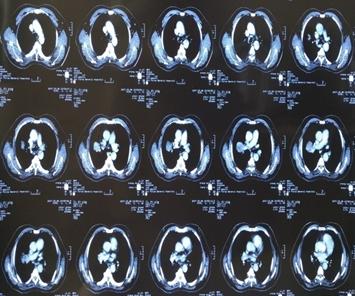

患者刘某某,男,65岁, 13年前因咳嗽、咳痰带血半年就诊,胸部CT示右上肺占位,支气管镜示右上叶前段支气管远端狭窄,活检病理:中低分化鳞癌。诊断:右上肺中低分化鳞癌,T4N1M0,IIIB期。

因二次全麻下气管插管出现哮喘无法手术,于2007年5月30至2007年6月28日进行局部放射治疗,同时给予对症支持治疗。照射剂量PTV(肿瘤外5mm)66GY/22f/30d;GTV(肿瘤边缘)70GY/22f/30d;GTV1(肿瘤内部)77GY/22f/30d;治疗期间,咳嗽缓解、无咯血,血常规 基本正常 范围,按计划完成治疗。